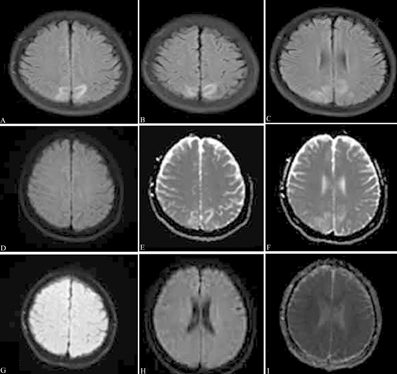

病例4:女性,18岁,因"G1P0孕40周,产程中出现四肢抽搐1 d"急诊就诊,入院查体:血压120/80 mmHg,嗜睡状态,双侧瞳孔等大等圆,直径2.5 mm,对光反射灵敏,眼底正常,病理反射未引出。头颅MRI示双侧顶枕区斑片状信号异常,T1低信号、T2及FLAIR高信号、DWI稍低信号、ADC高信号(图4)。考虑妊娠引起PRES,急行剖宫产后意识恢复,未再发抽搐。治愈出院。1个月后外院复查CT示双侧顶枕区病灶完全消失。1年后我院复查MRI示双侧顶枕区病灶完全消失(图4)。

患者女性,18岁,因"G1P0孕40周,产程中出现四肢抽搐1 d"入院,头颅MRI示双侧顶枕叶斑片状异常信号,液体衰减反转恢复序列呈高信号(A~C),弥散加权成像呈稍低信号(D),表观弥散系数图呈高信号(E~F);出院1年后复查MRI示病灶完全消失(G~I)